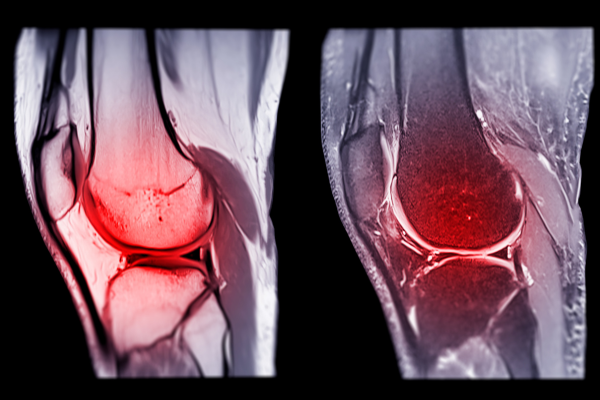

Our Knee Procedures

Knee Arthroscopy

ACL Reconstruction

PCL Reconstruction

Total Knee Replacement

Removal of Loose Bodies